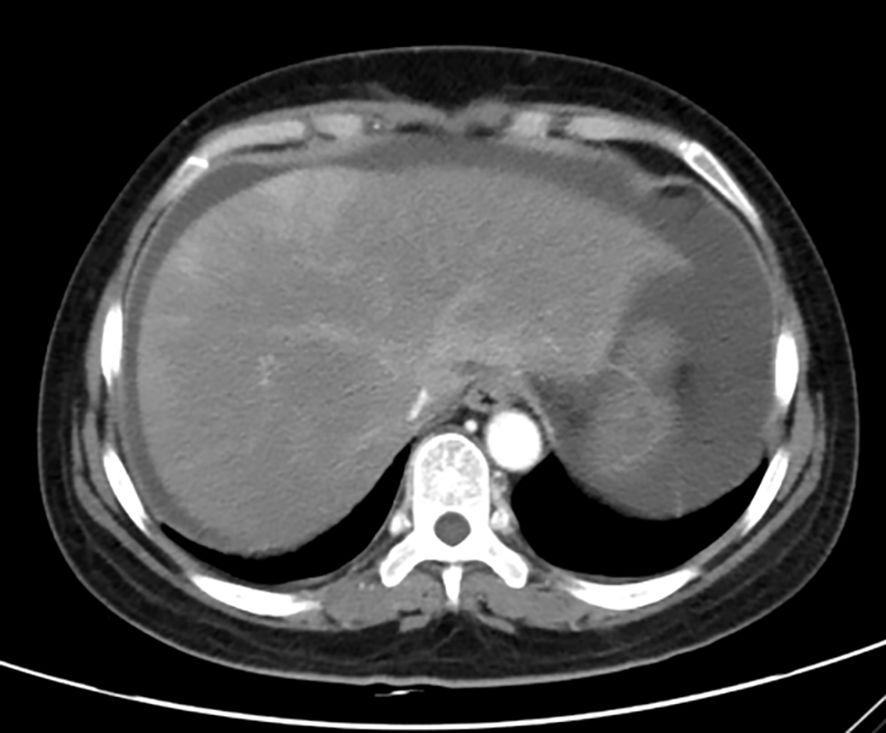

Unfortunately, two days later, her symptoms deteriorated. On examination, she had abdominal distention and positive mobility dullness, but her temperature was normal. She was conscious, and had no icteric sclera, and no obvious ecchymosis on the skin. Those results of blood RT on September 19th were as follow: white blood cells count at 11.75×109/L, hemoglobin at 102 g/L, platelet at 10×109/L. Comprehensive metabolic panel (CMP) showed: aspartate aminotransferase at 3980 U/L (≦ 40 IU/L), alanine aminotransferase at 1670 U/L (≦ 35 IU/L), creatinine at 117.2 ummol/L (≦ 90 ummol/L), uric acid at 742.3 ummol/L (≦ 357 ummol/L), urea at 14.5 ummol/L (≦ 7.5 ummol/L), Na+ at 128 mmol/l (≧ 137 mmol/L), prothrombin time (PT) at 42.30 sec, international normalized ratio (INR) at 3.96 sec, activated partial thrombin time at (APTT) 34.20 sec, thrombin time (TT) at 25.30 sec, fibrinogen (FIB) concentration at 0.71 g/L. The test of hepatitis A, B, C, E serologies was negative. T-lymphocyte subsets were normal, but interleukin-6 was abnormally elevated to 29.5 pg/ml (≦ 7 pg/ml). Accordingly, she was diagnosed with immune-mediated hepatitis G4 and acute liver failure. Immediately, the patient was transferred to intensive care unit (ICU) department at 8:00 PM on September 19th. At 10:00 PM, she went into delirium, and obvious ecchymosis appeared on her skin. The re-examined CMP results were as follow: Aspartate transaminase at 5329 U/L, alanine transaminase at 2384 U/L, total bilirubin (TBIL) at 56.99 IU/L (≦ 23 IU/L), direct bilirubin (DBIL) at 30.23 IU/L (≦ 4 IU/L), albumin at 32 g/L, PT at 62.50 sec, INR at 5.85 sec, APTT at 41.40 sec, TT at 27.80 sec, FIB concentration at 0.5 g/L, Hb at 83 g/L, platelet count at 12×109/L, blood ammonia at 210 IU/L (≦ 72 IU/L). The results of blood gas in emergency were as follow: PH at 7.362, PCO2 at 19.5 mmHg, PO2 at 155 mmHg, HCO3- at 14.4 mmol/L, BE- at 14.3 mmol/L, Na+ at 125mmol/L, Lactic acid at 15 mmol/L, glucose at 8.3 mmol/L. Computer tomography scan revealed that there were massive abdominal and pelvic effusion, and suspected drug-induced liver injury (Figure 1). A liver biopsy was not performed for the sake of poor coagulation and low platelets.

CT scan of the abdomen showing a transverse cross-section of the liver, with distinct light and dark areas indicating varying tissue densities. The spinal column is visible at the bottom.

Figure 1. Enhanced CT scan of liver (Decreased and uneven density of liver parenchyma, increased abdominal and pelvic effusion, thus, drug-induced liver injury was considered).